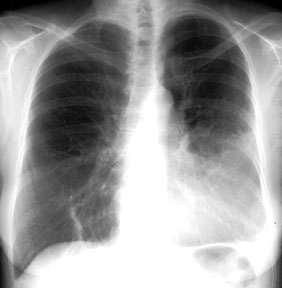

1. http://www.meddean.luc.edu/lumen/meded/medicine/pulmonar/images/xray/173l.jpg Normal chest